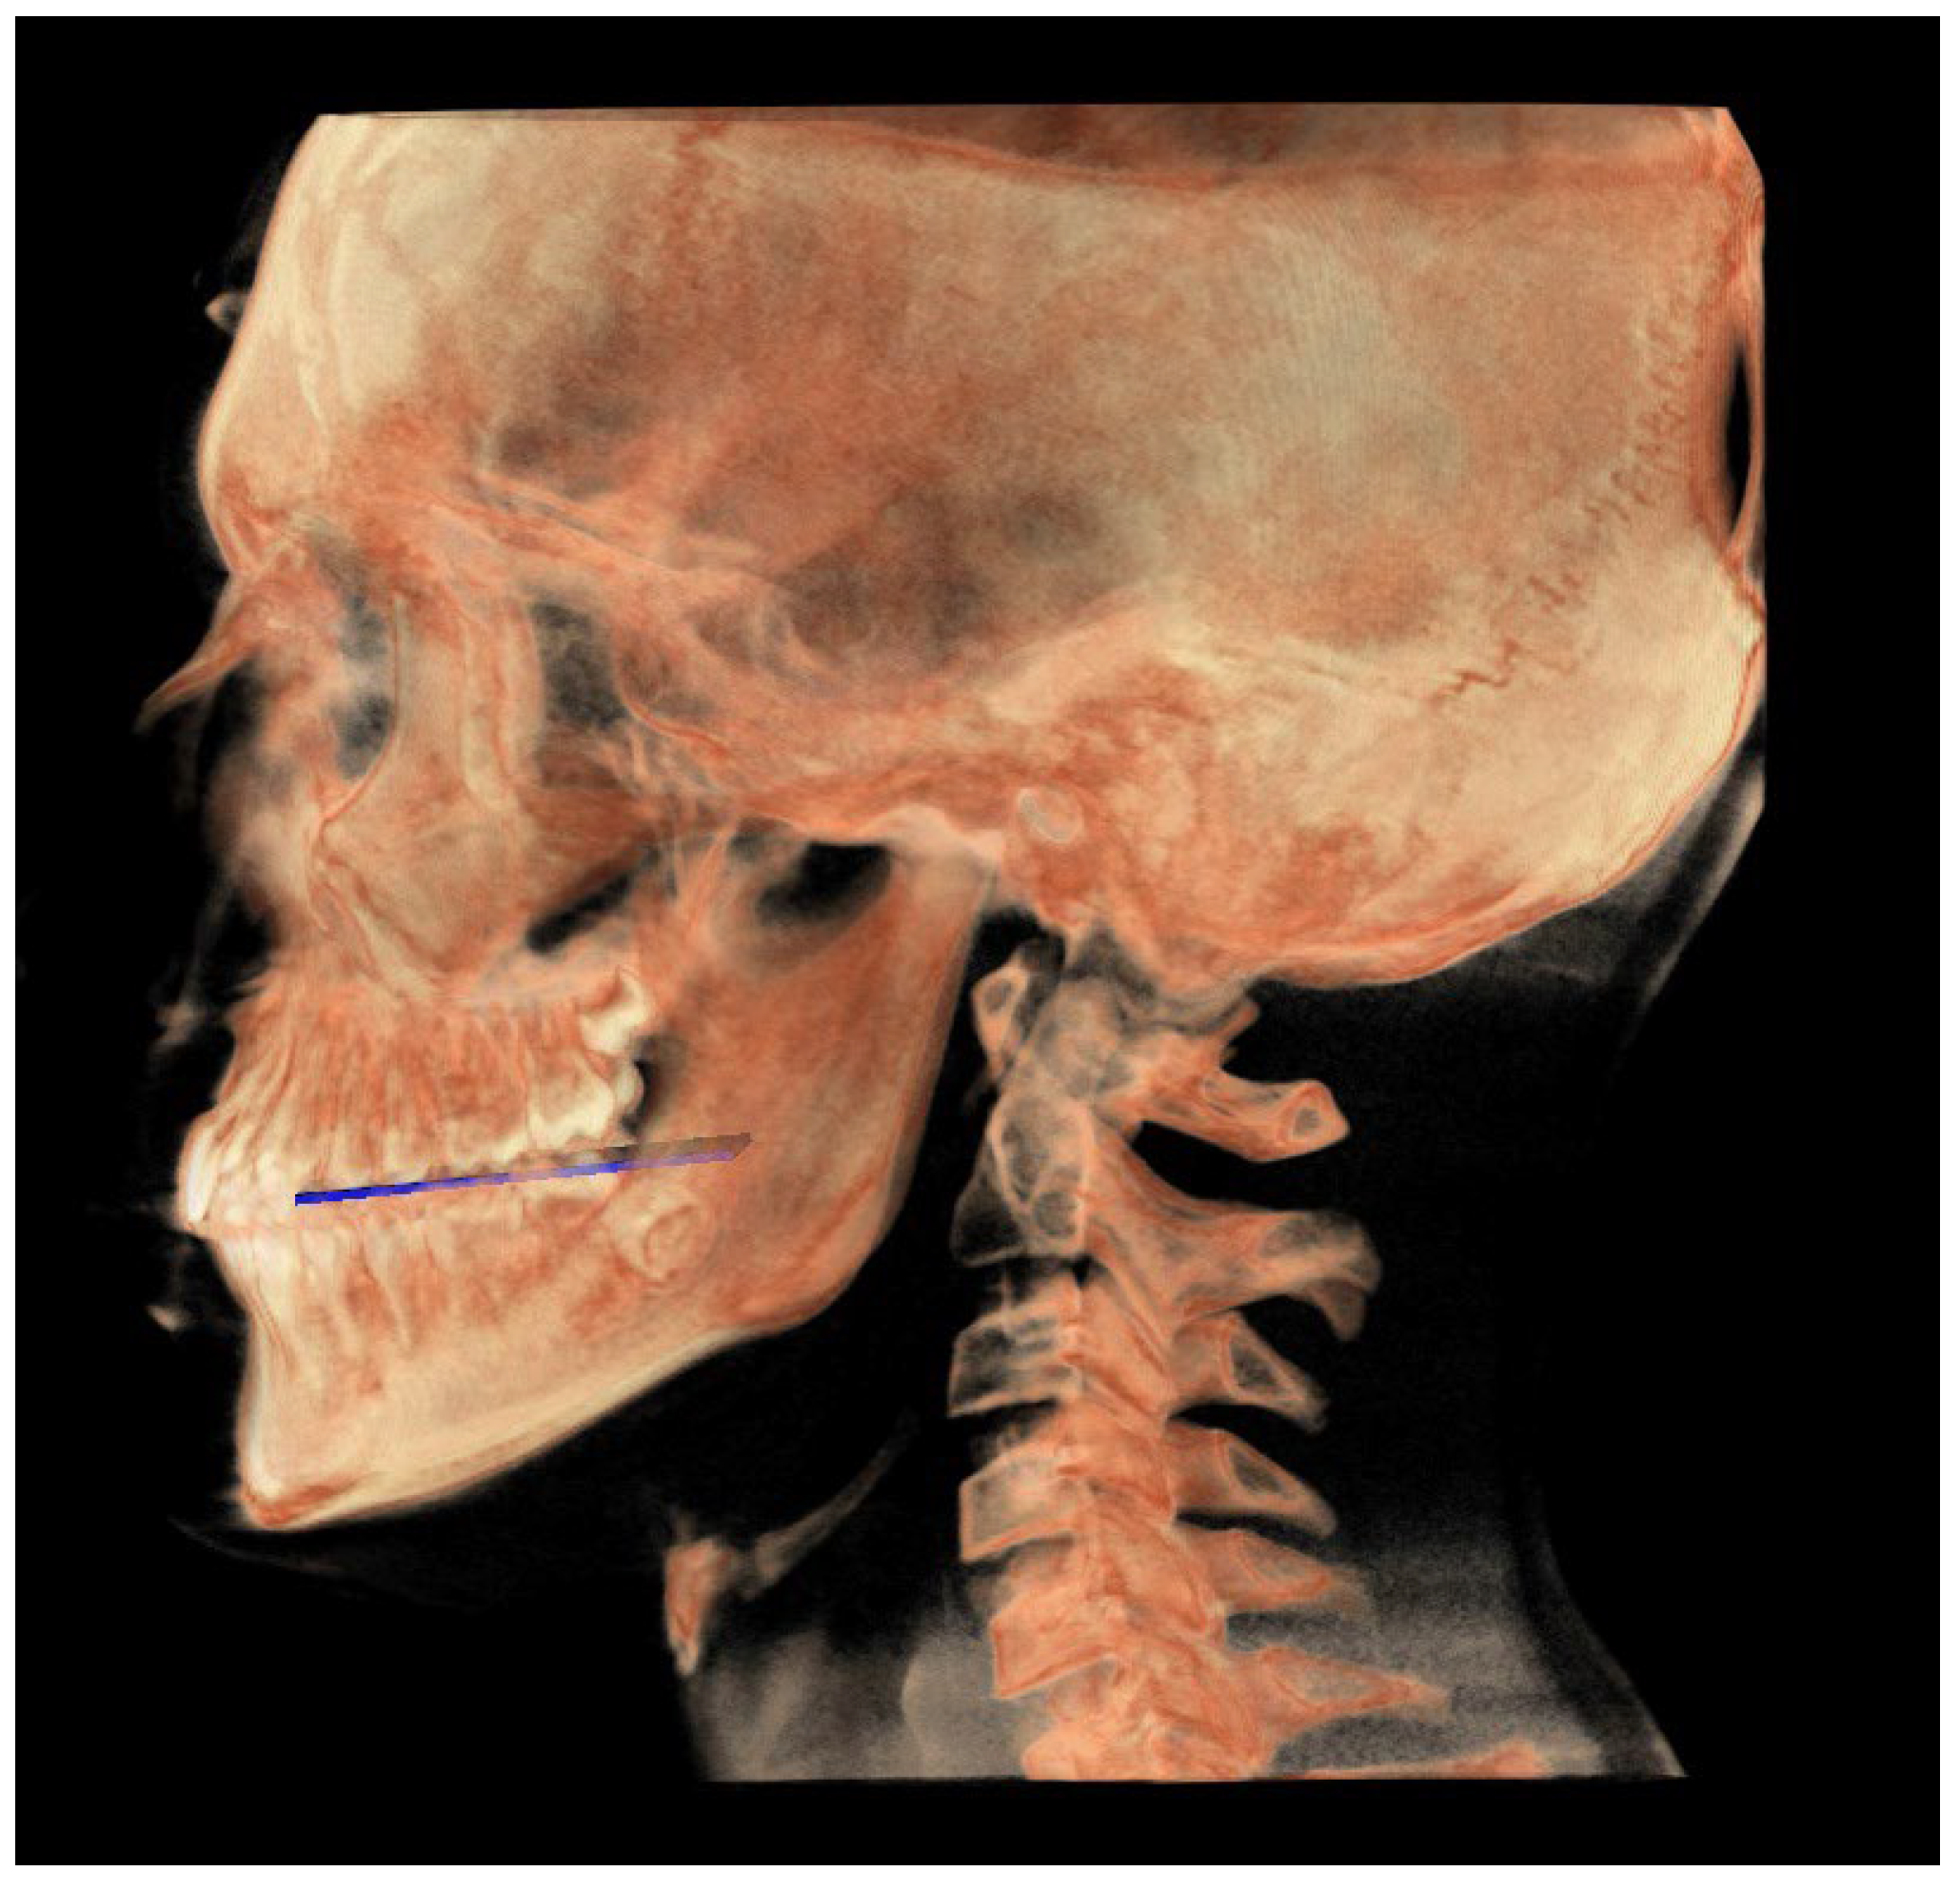

- The functional occlusal plane (FOP) (Figure 6) was identified by the posterior occlusal contact right side (rPoc), posterior occlusal contact left side (lPoc) and the middle point between the right and left anterior occlusal contact (mAoc). To adequately locate the mAoc, it is advisable to draw a line on the transversal view from the right mesial premolar contact to the left one to have a reference along which measure the distance.

| FOPn | FOP neutral, plane perpendicular to the PMn passing through Poc |

| Posterior occlusal contact, right side (rPoc) | Most supero-distal contact point of the first molars, right side | / | / |

| Posterior occlusal contact, left side (lPoc) | Most supero-distal contact point of the first molars, left side | / | / |

| Anterior occlusal contact, right side (rAoc) | Most mesial contact point between the first premolars, right side | / | / |

| Anterior occlusal contact, left side (lAoc) | Most mesial contact point between the first premolars, left side | / | / |

| Middle point between right and left Aoc (mAoc) | Middle point between the rAoc and lAoc | Middle point between the rAoc and lAoc | Middle point between the rAoc and lAoc |

| FOP neutral (FOPn) | Plane normal to the PMn passing through rPoc and lPoc |